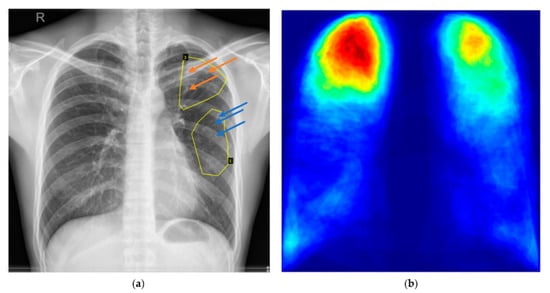

:1. Introduction

2. Annotations of Lung Abnormalities for TB Patients in Shenzhen CXR Dataset

2.1. Annotations in JSON Format and Visualization